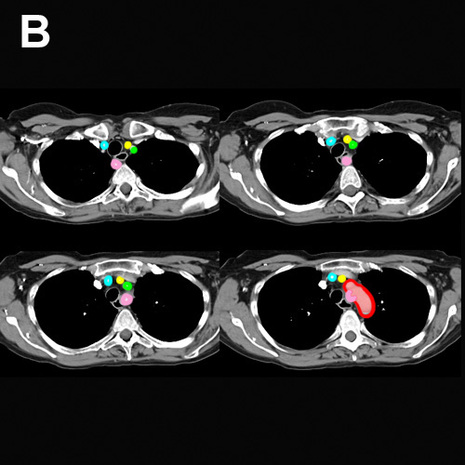

Image B shows labels on the structures in these CT images.

The aorta is outlined in red. The right subclavian artery has an anomalous origin, coming off as the last branch of the aortic arch and passing posterior to the trachea and esophagus. This is called an aberrant right subclavian artery. The aberrant vessel is shown in pink. The right common carotid artery (there is no brachiocephalic artery in this case, since the right common carotid artery and right subclavian artery do not arise from a common trunnk) is shown in blue, the left common carotid artery in yellow and the left subclavian artery in green.